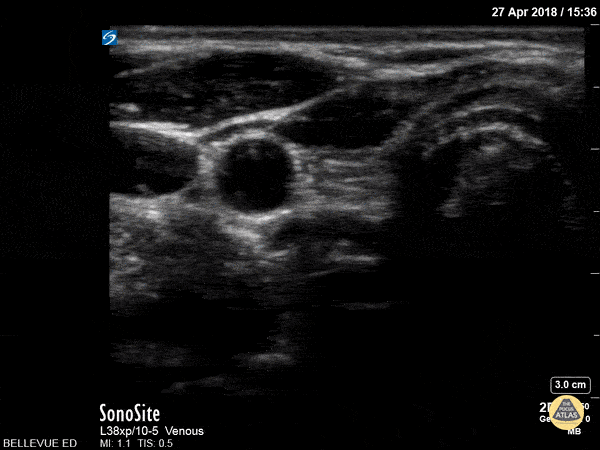

Soft Tissue - Thyroid Right Lobe

In this view we see half of the thyroid gland, which has similar echogenicity to the liver. The thyroid isthmus overlies the trachea and it extends into the right thyroid lobe which lies medial to the pulsatile right carotid artery. Lateral to the carotid we see the right internal jugular vein. Superficial to the IJ and carotid we see the large sternocleidomastoid muscle; medial to that, superficial to the trachea and thyroid on the right side of the screen, are the strap muscles. Hannah Kopinksi and Dr. Lindsay Davis - NYU Emergency Medicine